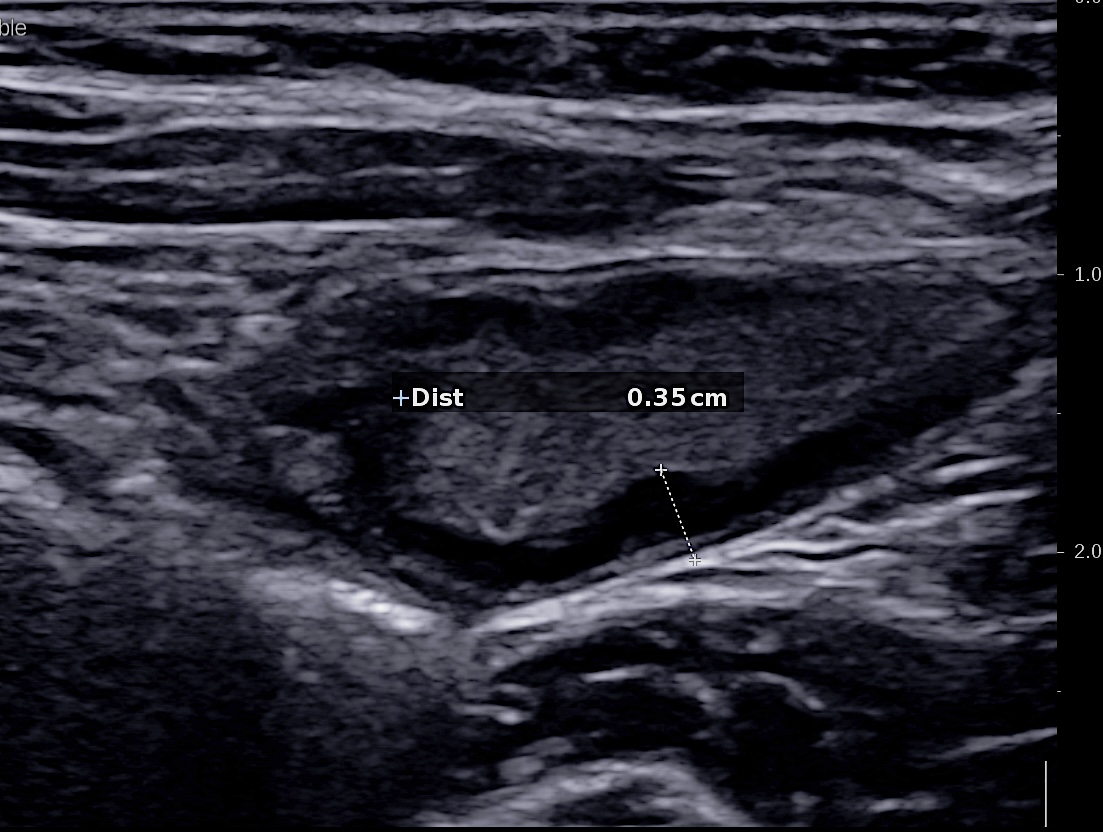

C'est l'élément le plus sensible et le plus reproductible (inter et intra observateur)

Au delà de 3 mm la paroi est épaissie.

Elle est très importante si on veut être fiable et reproductible et pouvoir suivre l'évolution de l'inflammation

L'épaississement se mesure entre la muqueuse (hypoéchogène) et la musculeuse (hypoéchogène),

L'échographie est la technique radiologique qui a la meilleure résolution (millimètre)